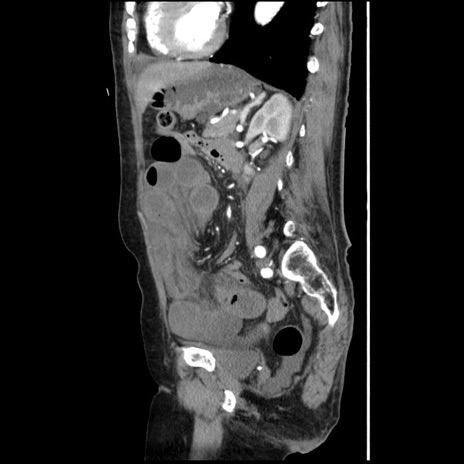

症例1(矢状断像)

【症例】80歳代女性

【主訴】腹痛

【現病歴】8時間前から腹痛あり来院。

【既往歴】糖尿病、脂質異常症、子宮体癌にて子宮全摘術

【身体所見】意識清明・会話良好だが腹痛で苦悶様、全腹部にわたって反跳痛と圧痛あり

【データ】WBC 13600、CRP 0.14、LDH 224、CK 90